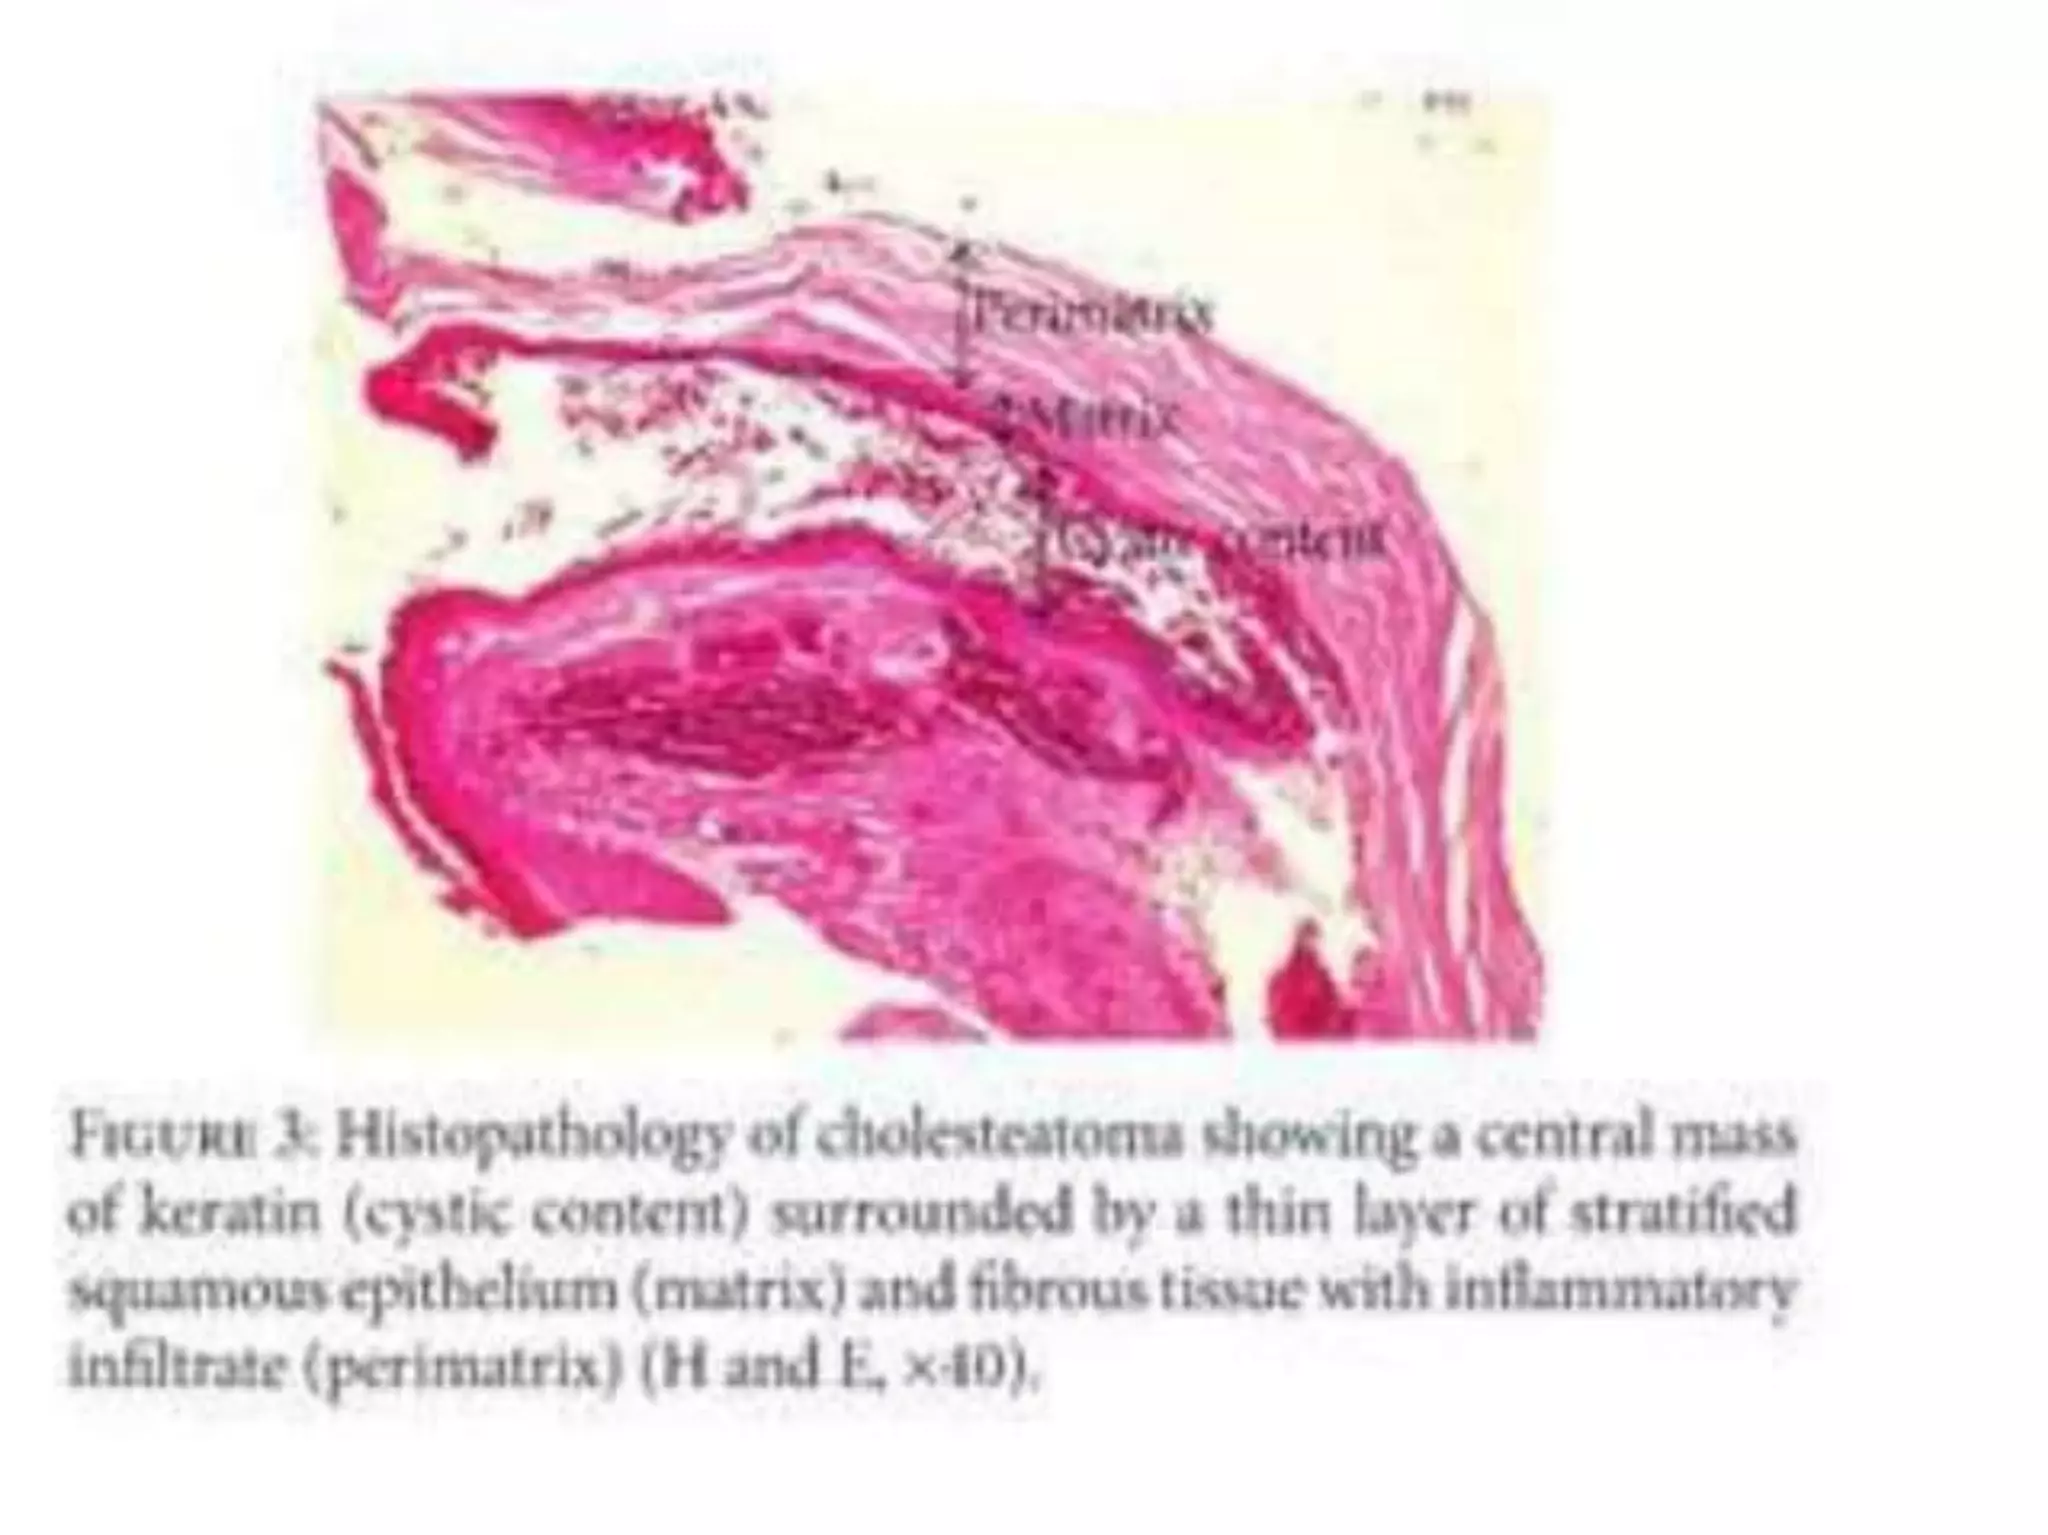

Chronic otitis media is a chronic inflammation of the middle ear and mastoid cavity that presents with recurrent ear discharge through a perforated eardrum. It has several subtypes depending on the state of the eardrum perforation and epithelium. It can be caused by prior acute otitis media, genetics, environment, eustachian tube issues, gastroesophageal reflux disease, craniofacial abnormalities, or immune deficiency.